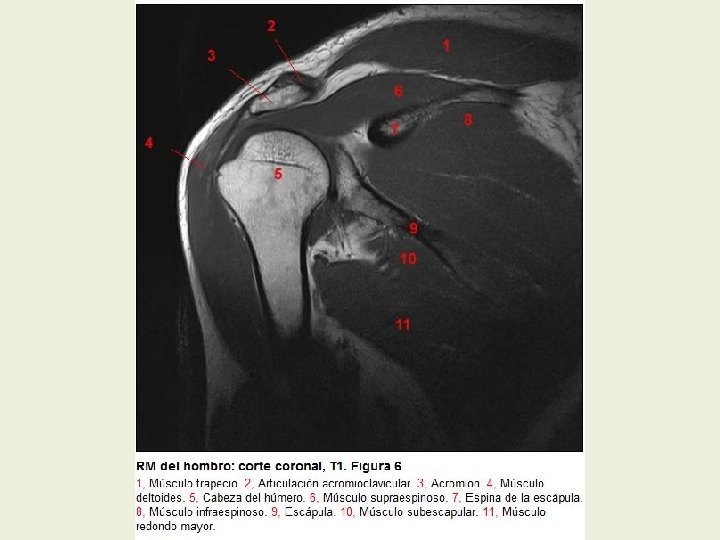

Hombro Cortes coronales RMN